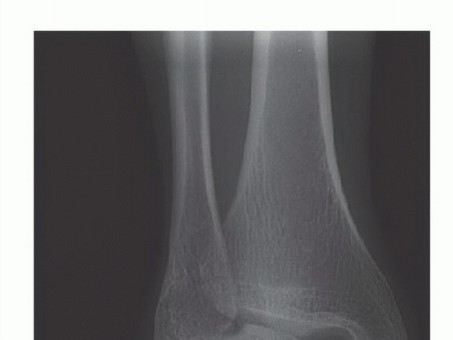

DEFINITION Osteochondral lesions of the talus (OLT) are common conditions that can involve both the cartilage…